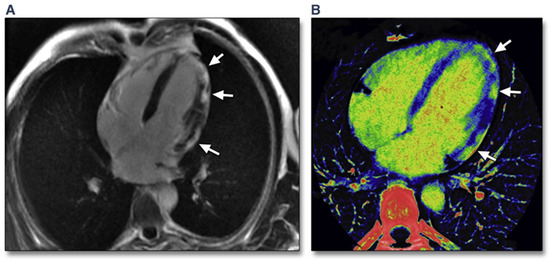

- von Olshausen, G.; Hyafil, F.; Langwieser, N.; Laugwitz, K.L.; Schwaiger, M.; Ibrahim, T. Detection of acute inflammatory myocarditis in Epstein Barr virus infection using hybrid 18F-fluoro-deoxyglucose-positron emission tomography/magnetic resonance imaging. Circulation 2014, 130, 925–926. [Google Scholar] [CrossRef] [PubMed] [Green Version]

- Nensa, F.; Poeppel, T.D.; Krings, P.; Schlosser, T. Multiparametric assessment of myocarditis using simultaneous positron emission tomography/magnetic resonance imaging. Eur. Heart J. 2014, 35, 2173. [Google Scholar] [CrossRef] [Green Version]

- Nensa, F.; Kloth, J.; Tezgah, E.; Poeppel, T.D.; Heusch, P.; Goebel, J.; Nassenstein, K.; Schlosser, T. Feasibility of FDG-PET in myocarditis: Comparison to CMR using integrated PET/MRI. J. Nucl. Cardiol. 2018, 25, 785–794. [Google Scholar] [CrossRef]